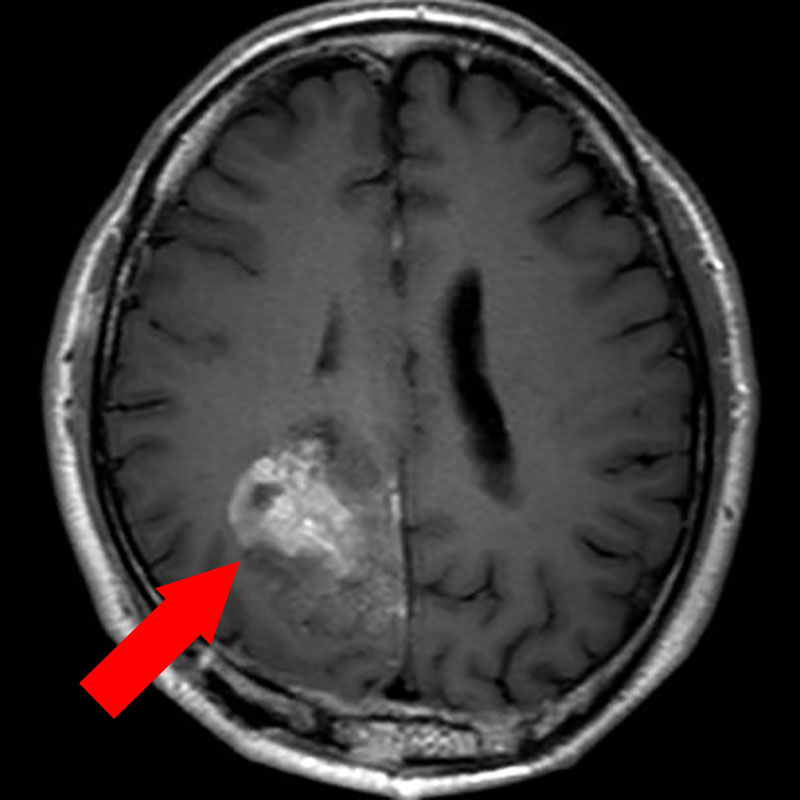

断層撮影

手術前1

手術前2